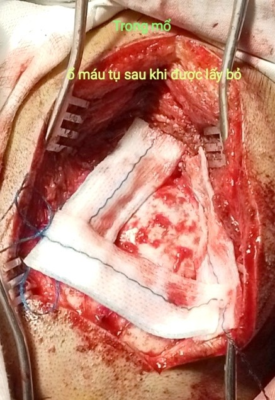

Hình 2. Hình ảnh đường vỡ xương chẩm, máu tụ trong mổ

Ca mổ diễn ra thuận lợi, lấy khối máu tụ, giải phóng chèn ép tiểu não. Kết quả Ctsccan sau mổ sạch máu tụ.

Hình 3. Máu tụ được lấy bỏ Hình 4. CT scan sau mổ